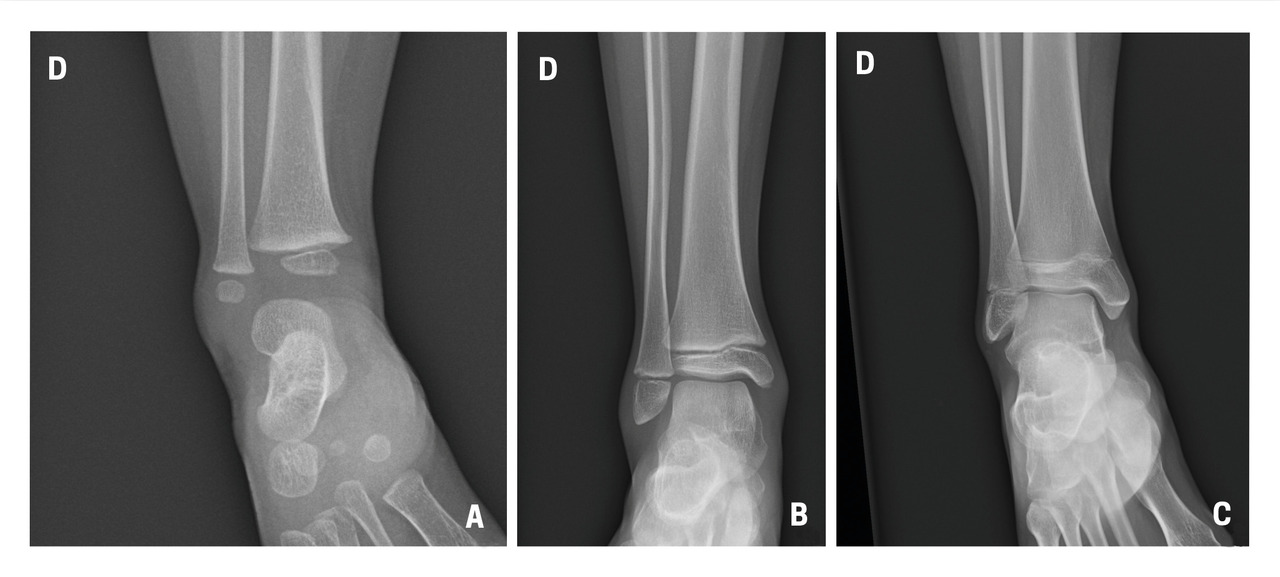

Il n’y a pas de consensus sur des tests cliniques (critères d’Otta­wa…) car ils ont une faible sensi­bilité sur les fractures peu ou non déplacées.4 En cas de doute à l’examen clinique, il est donc nécessaire de demander au moins deux incidences : face et profil. Par ailleurs, la cheville étant initialement une matrice cartilagineuse qui va pro­gressivement s’ossifier, la lecture des ­radiographies est parfois difficile chez l’enfant, dont les cartilages de croissance sont encore visibles (fig. 1). Dans environ 20 % des traumatismes, une fracture est retrouvée, notamment des avulsions de la pointe de la fibula, signe d’entorse grave, dont la prise en charge doit être rigoureuse pour éviter des instabilités chroniques.

Le diagnostic différentiel est principalement constitué par les fractures. Celles-ci sont spécifiques du fait des particularités de l’os pédiatrique, et le tableau clinique n’est pas toujours aussi flagrant que chez l’adulte. Il n’est pas rare de voir des enfants conserver un appui partiel sur des chevilles fracturées. Dans environ 20 % des traumatismes en inversion, il existe une avulsion de la pointe de la fibula8 (fig. 2), qui doit être recherchée et traitée par une botte en résine durant un mois, quel que soit l’âge. Les décollements épiphysaires de la malléole externe sont beaucoup plus rares que ce qui a longtemps été cru6, et leur pronostic fonctionnel semble bon quel que soit le traitement.